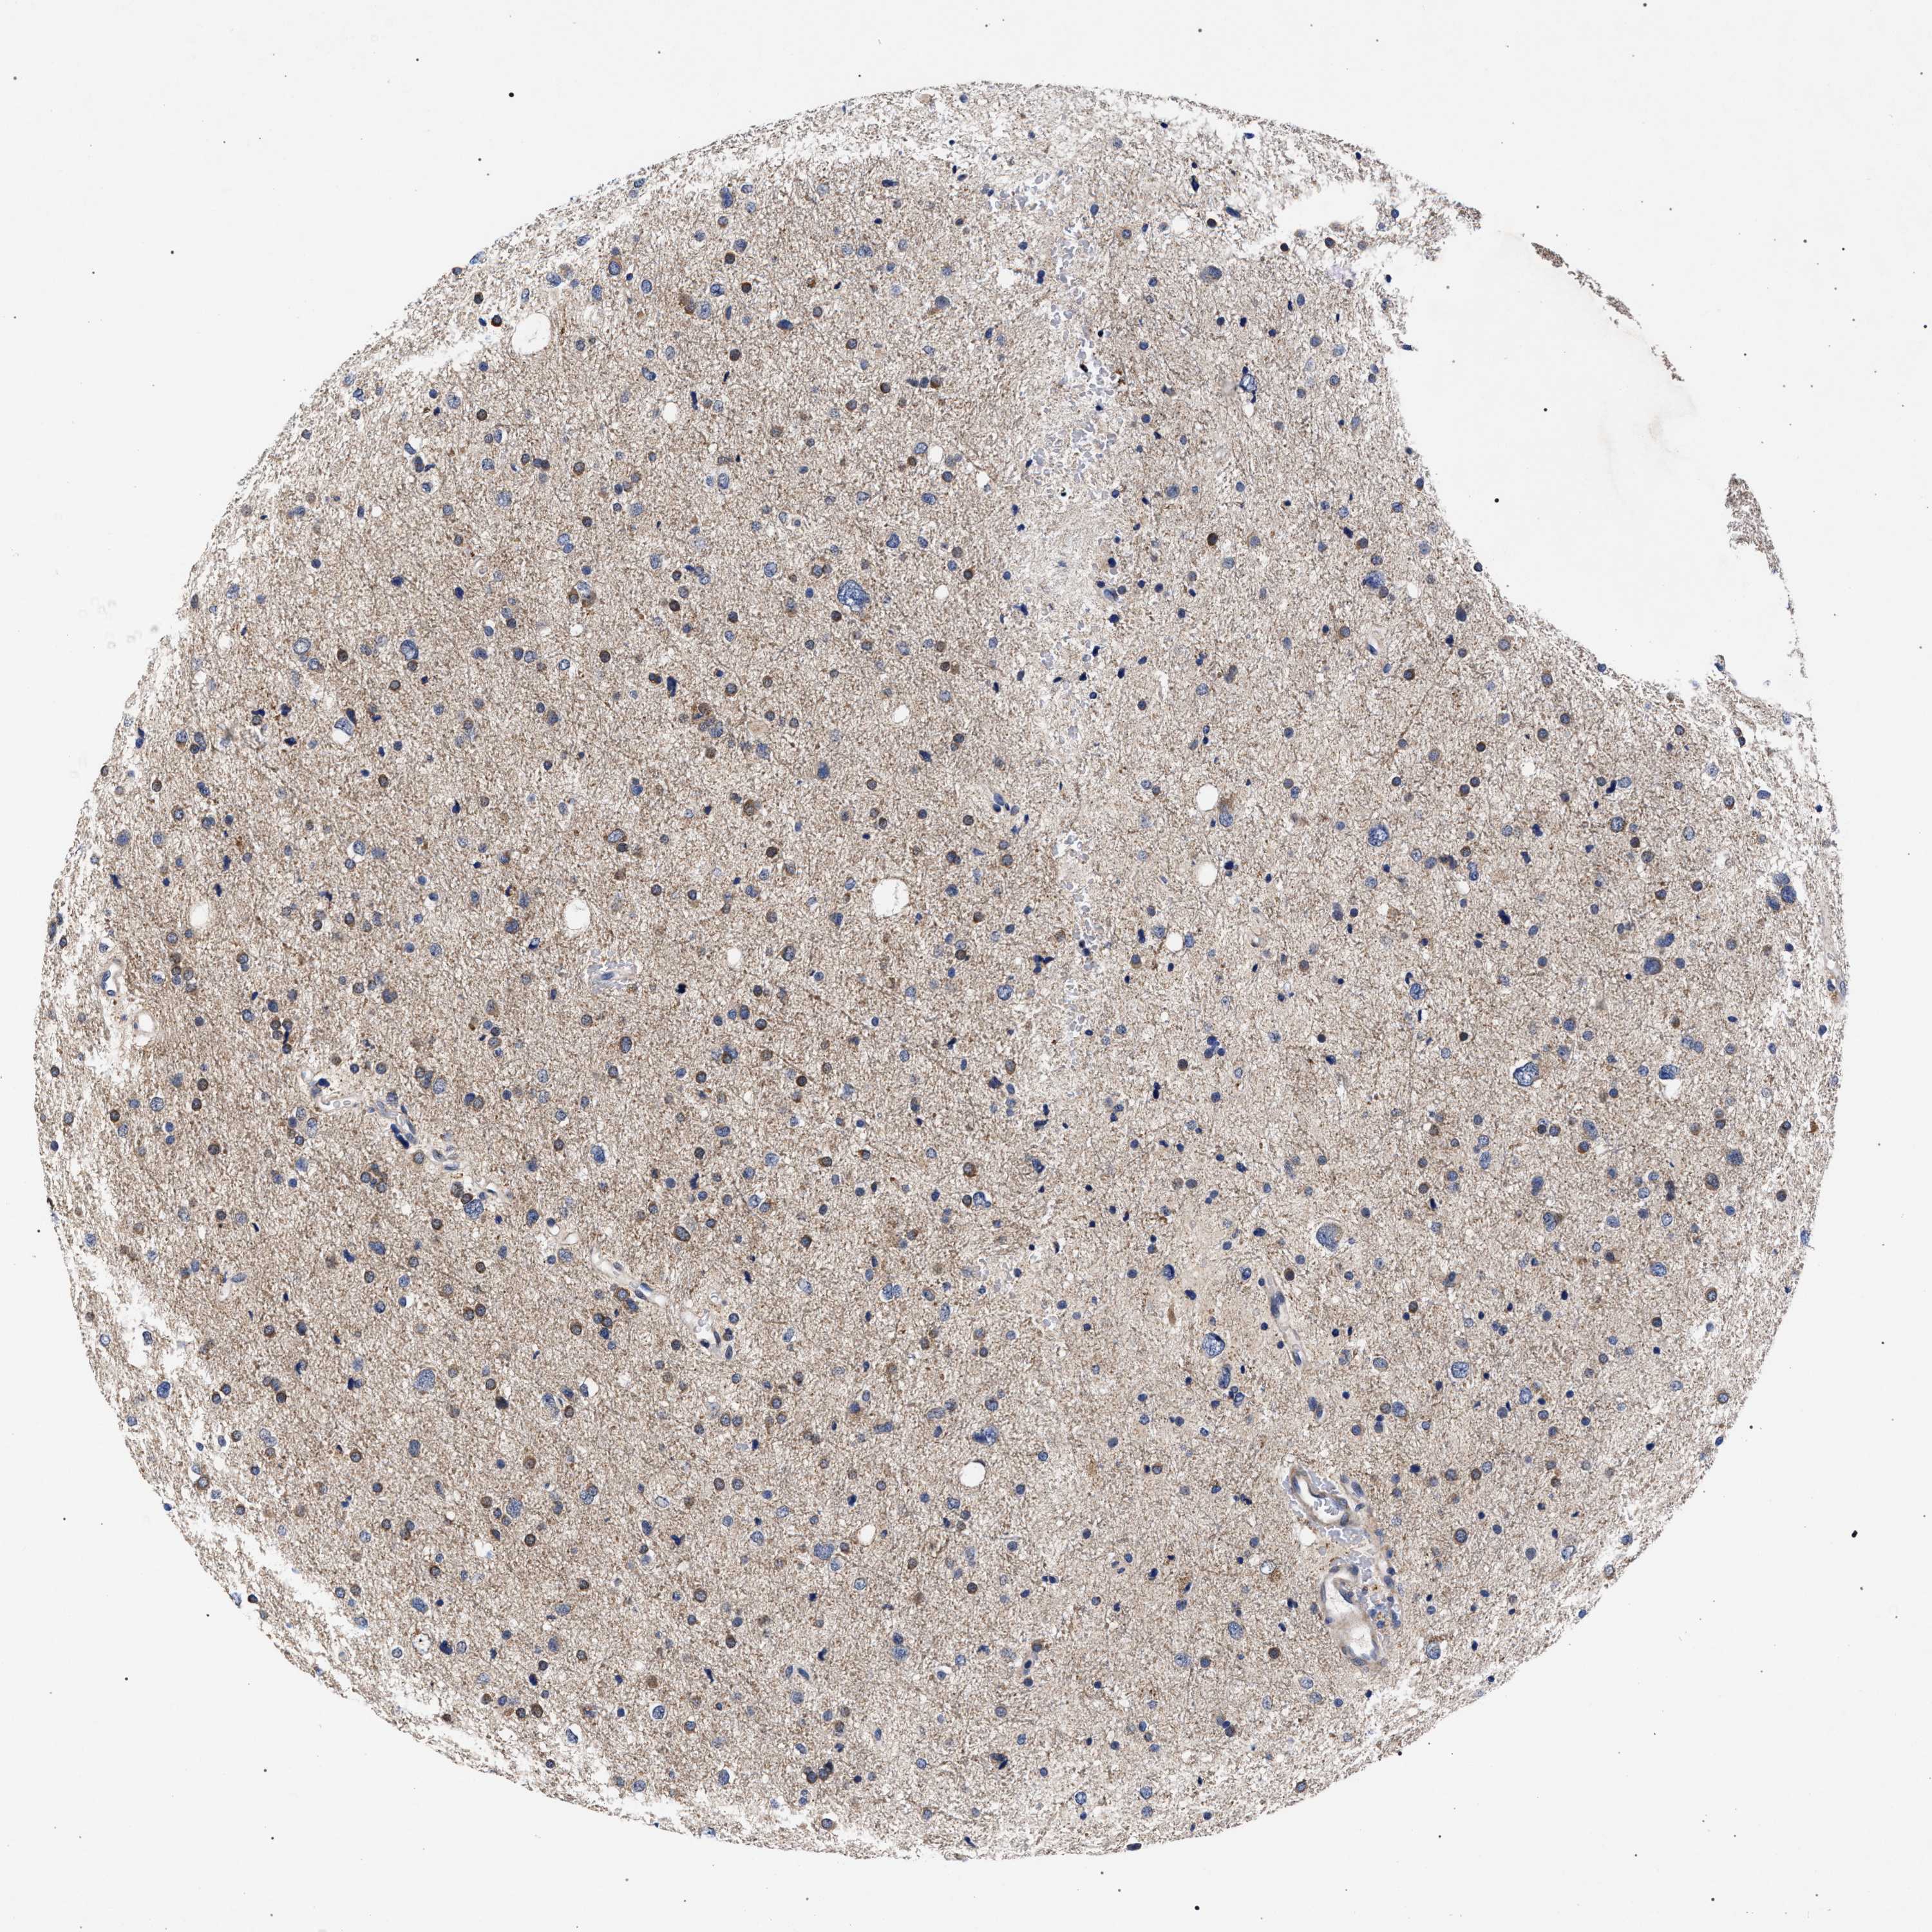

GLIOMA - Protein expressioni

A mouse-over function shows sample information and annotation data. Click on an image to view it in a full screen mode. Samples can be filtered based on level of antibody staining by selecting one or several of the following categories: high, medium, low and not detected. The assay and annotation is described here.

Note that samples used for immunohistochemistry by the Human Protein Atlas do not correspond to samples in the TCGA dataset.

Antibody stainingi

Antibody staining in the annotated cell types in the current human tissue is reported as not detected, low, medium, or high, based on conventional immunohistochemistry profiling in selected tissues. This score is based on the combination of the staining intensity and fraction of stained cells.

Each image is clickable and will lead to virtual microscopy that enables deeper exploration of all samples and also displays staining intensity scores, fraction scores and subcellular localization as well as patient and tissue information for each sample.

Antibody HPA021261

Antibody HPA021325

Staining

High

Medium

Low

Not detected

Intensity

Strong

Moderate

Weak

Negative

Quantity

>75%

75%-25%

<25%

None

Location

Nuclear

Cytoplasmic/membranous

Cytoplasmic/membranous,nuclear

Glioma, malignant, High grade

Glioma, malignant, Low grade